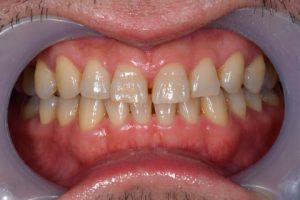

治療前

治療後

治療期間 11回(4ヶ月)

費用 ・ハイブリッドインレー7本

・ジルコニアクラウン2本

・ホワイトニング:5回

合計:430,500円

治療リスク・副作用 ・詰め物、被せ物をする時は自分の歯を削ることになります

・歯ぎしり・食いしばりが強い方は、セラミックが割れてしまうことがあります。